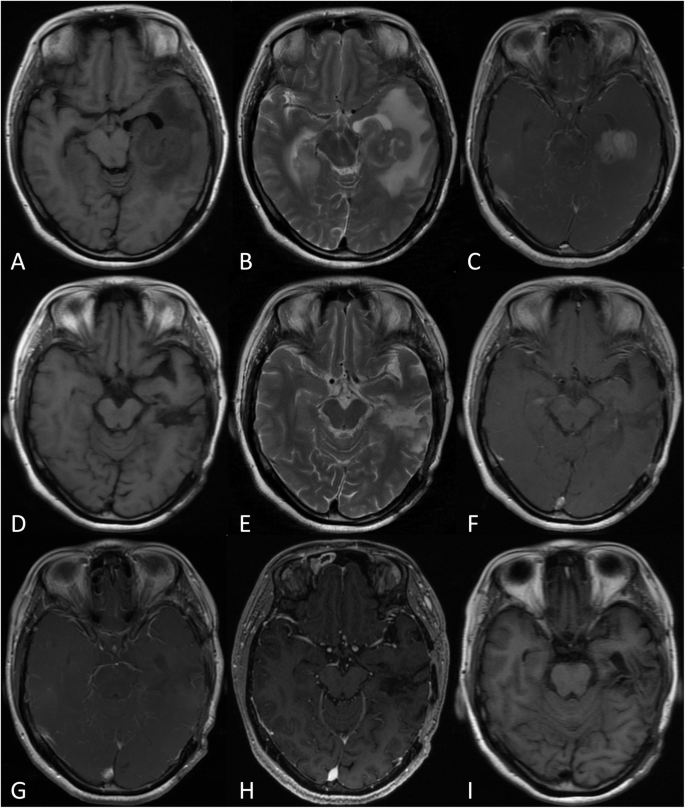

With a median follow-up of 30 months (range 1–110), the mean OS and PFS of all patients were 16.1 months and 6.2 months, respectively. Patients who underwent surgical resection had a mean OS of 23.4 months and a PFS of 8.6 months versus 11.2 months and 4.6 months for those who had a brain biopsy performed (Table 1, Figs. 1 and 2). Table 3 summarizes the results from univariate analyses of OS and PFS. Younger age, lower IESLG score, not involving deep structures and resection were favourable prognostic factors for OS. In addition, deep structure, resection and no complications were identified as favourable prognostic factors for PFS. Sex, KPS, duration of symptoms, number of tumours, maximum diameter of the target, and changes in symptoms were not significant prognostic factors for survival (P > 0.05). After univariate analysis, multivariable Cox regression analysis was performed with the 5 statistically significant variables, which showed that deep structures not involved and resection were favourable prognostic factors for PCNSL (Table 4). There is a typical example of the resection group in Fig. 3.

A 42-year-old men who presented with headache for 1 month. MRI (a, b and c) shows a contrast-enhancing solitary lesion with a diameter of 3.5 cm in the left temporal lobe. He underwent surgery with a craniotomy and gross total resection. The symptoms of headache were improved obviously. MRI examination (d, e and f) was taken at 1 week after surgery, which shows the lesion was removed completely. And MRI of 3 months (g), half a year (h) and 1 year (i) after surgery show that there was no recurrence of the tumor

PCNSL has typical radiological appearances, which often show diffuse homogeneous contrast enhancement and surrounding vasogenic oedema on MRI (Fig. 3). There are also many atypical imaging features that may mimic other diseases and add to the diagnostic difficulty. Recently, various advanced imaging techniques have also been used in the diagnosis and prognostication of PCNSL, including diffusion tensor imaging (DTI), diffusion-weighted imaging (DWI) and magnetic resonance spectroscopy (MRS). Toh et al. [11] found that the fractional anisotropy of DTI is significantly lower in PCNSL than in glioblastoma. In addition, PCNSL has markedly higher choline/creatine and choline/N-acetyl aspartate ratios on MRS than other glial tumours [12]. In our present study, we also observed that the most common location of PCNSL was the supratentorial location (51.4%), followed by the infratentorial and deep locations (24.3%). This is consistent with a retrospective analysis of the clinical data of 100 patients with PCNSL, which was reviewed and analysed by Küker et al [13] At the same time, we found that 65% of PCNSL patients had solitary lesions, and 35% had multiple lesions. The mean maximum diameter of the tumour was 29.9 mm.